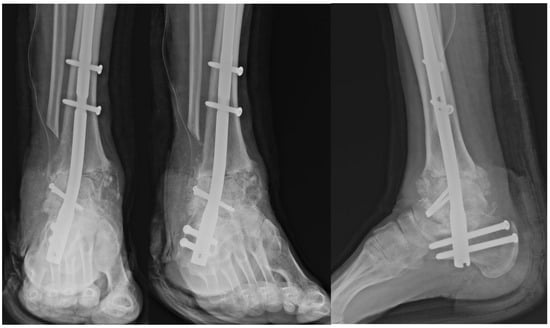

Autologous bone grafts were also utilized intraoperatively. The excised fibular shaft and resected talar fragments were morselized using a bone mill and used as local cancellous graft material to fill any residual defects and augment the fusion site (Figure 4). The shaped allograft was inserted into the prepared talar void and temporarily stabilized with multiple Kirschner wires (Figure 5). Final fixation was achieved with a retrograde intramedullary (IM) nail system (Stryker® T2 Ankle Arthrodesis Nail), inserted from the plantar surface of the calcaneus through the talus into the tibia. Additional fixation with two 3.5 mm cannulated screws targeting the residual talar head or anterior portion of the graft was applied in cases where enhanced rotational or axial stability was deemed necessary (Figure 6).

Figure 6. Postoperative radiograph demonstrating fixation of the talar allograft to the residual talar head using two 3.5 mm cannulated screws for structural stability.